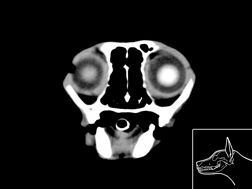

Atlas cérébral du chat IRMT2

IRM T2

31 coupes

Atlas cérébral du chat IRMT1

IRM T1

>> 31 coupes

Atlas cérébral du chat SCTM

Scanner tissu mou

>> 18 coupes

Atlas cérébral du chat SCTO

Scanner tissu osseux

>> 18 coupes